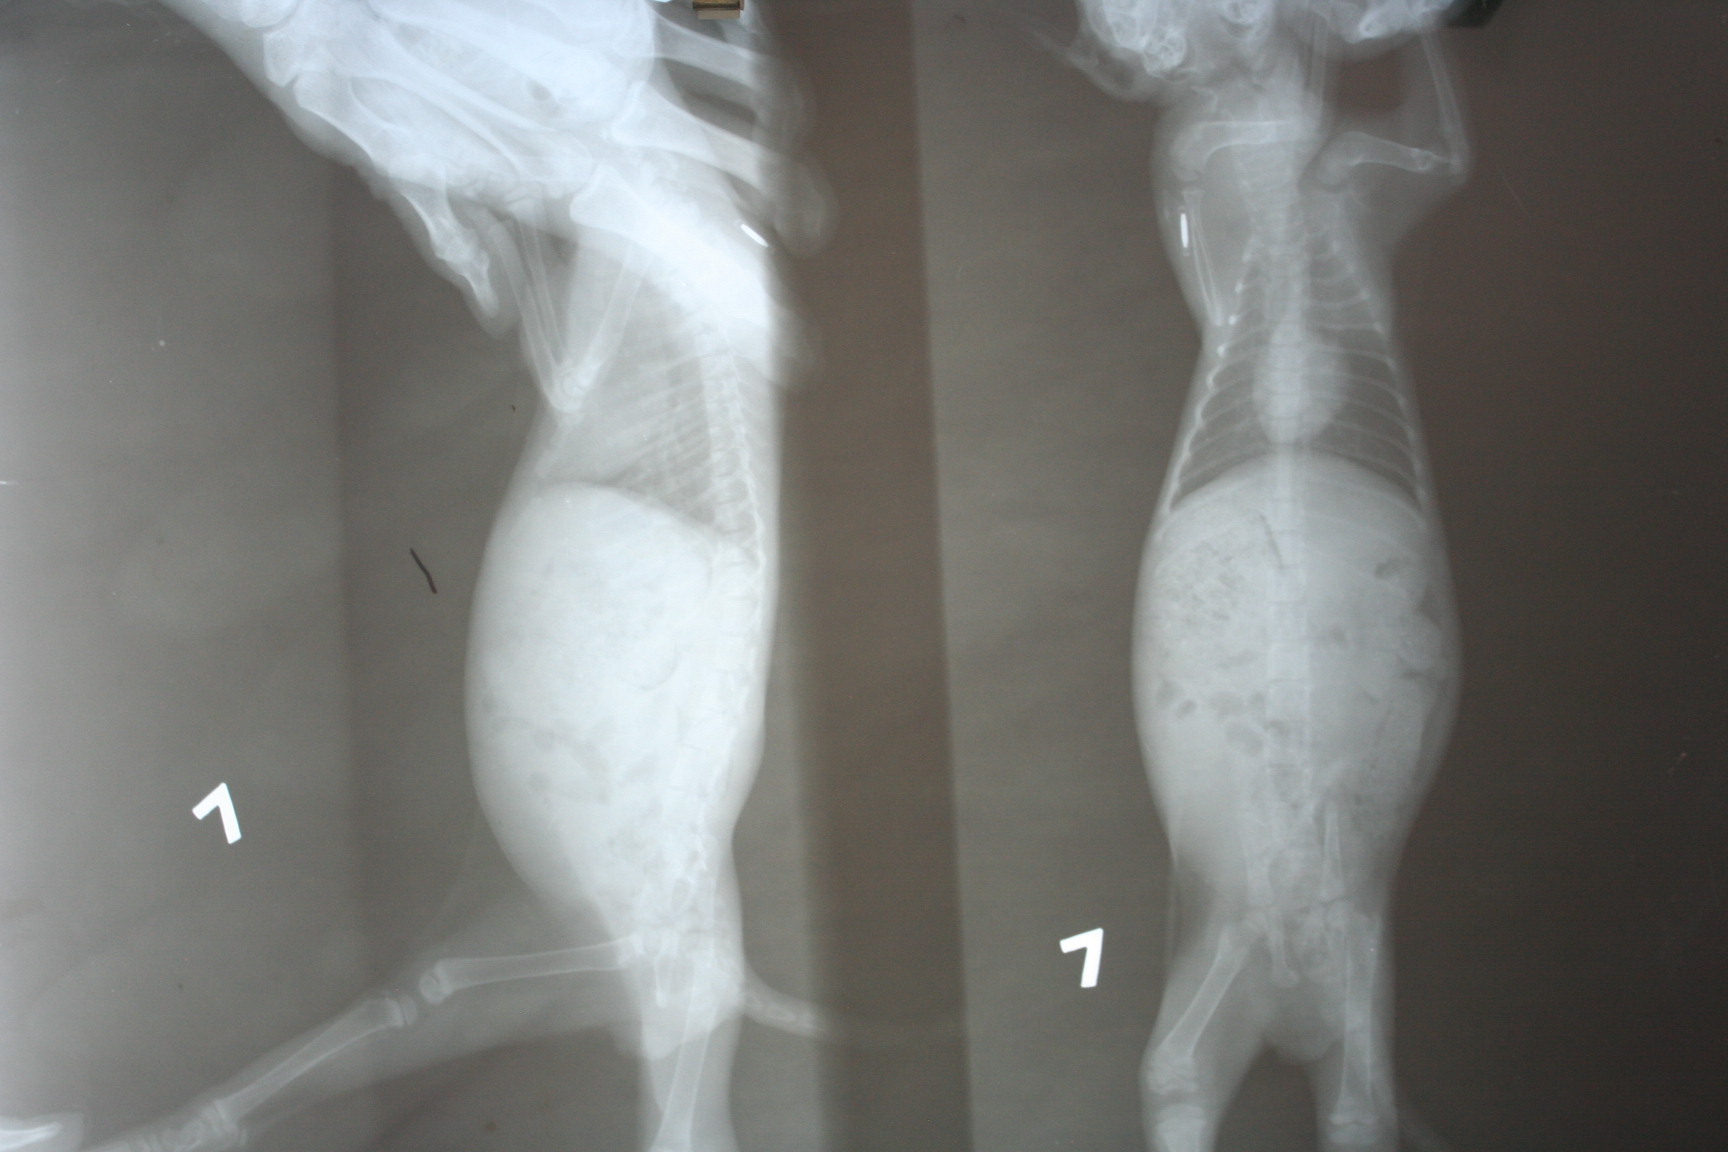

主題: 後腳癱瘓小貓,好不容易治好後腳後,卻因不敵貓瘟而變成飛翔的小天使 申請者姓名: 涂儷穎 花色: 申請日期: 2012-10-20 00:56:42 申請者部落格: 申請者臉書網址: 所在縣市/合作醫院: 高雄市/回生動物醫院 治療費用: 8460元 需求人數: 20人 已結案 (2013-06-27 13:46:29) 報名人員: Elsa Tu(已付款)、Elsa Tu(已付款)、Lai Fhifhi(已付款)、Mei Fujihala(已付款)、kelly(已付款)、Crystal Lin、dplantis(已付款)、Liyun Chang(已付款)、Bella Chen(已付款)、philip(已付款)、philip(已付款)、teijo53(已付款)、Larry Hey(已付款)、Larry Hey(已付款)、Aslan Chen(已付款)、Bei Bei Wang(已付款)、徐雅嬪(已付款)、May Chuang(已付款)、Elsa Tu(代Kiki Chen報名)(已付款)、Kelly Kao(已付款)、阿呆的貓(已付款)、 候補人員: 動物病情說明: 10/2上班途中救了後腳癱瘓的小貓,因為擔心他根本無法在街上生活,所以送他到回生動物醫院治療,想說治療好後要幫她找個幸福的家

脊椎受傷的小貓醫藥費明細如下:

•噴除蚤藥100元

•X光片400元

•10/3、10/5、10/7、10/10針灸費用

300*4=1200元

•10/2-10/16住院治療費用

300*14=4200元

•10/15小病毒腸炎檢查600元

10/15傳染性腹膜炎檢查500元

10/15二合ㄧ檢查500元

10/15全身血液檢查1500元

10/15抗體干擾素注射400元

•10/16小貓離開後的火化費用500元

所以以上全部的醫療費打完9折為9400*0.9=8460元